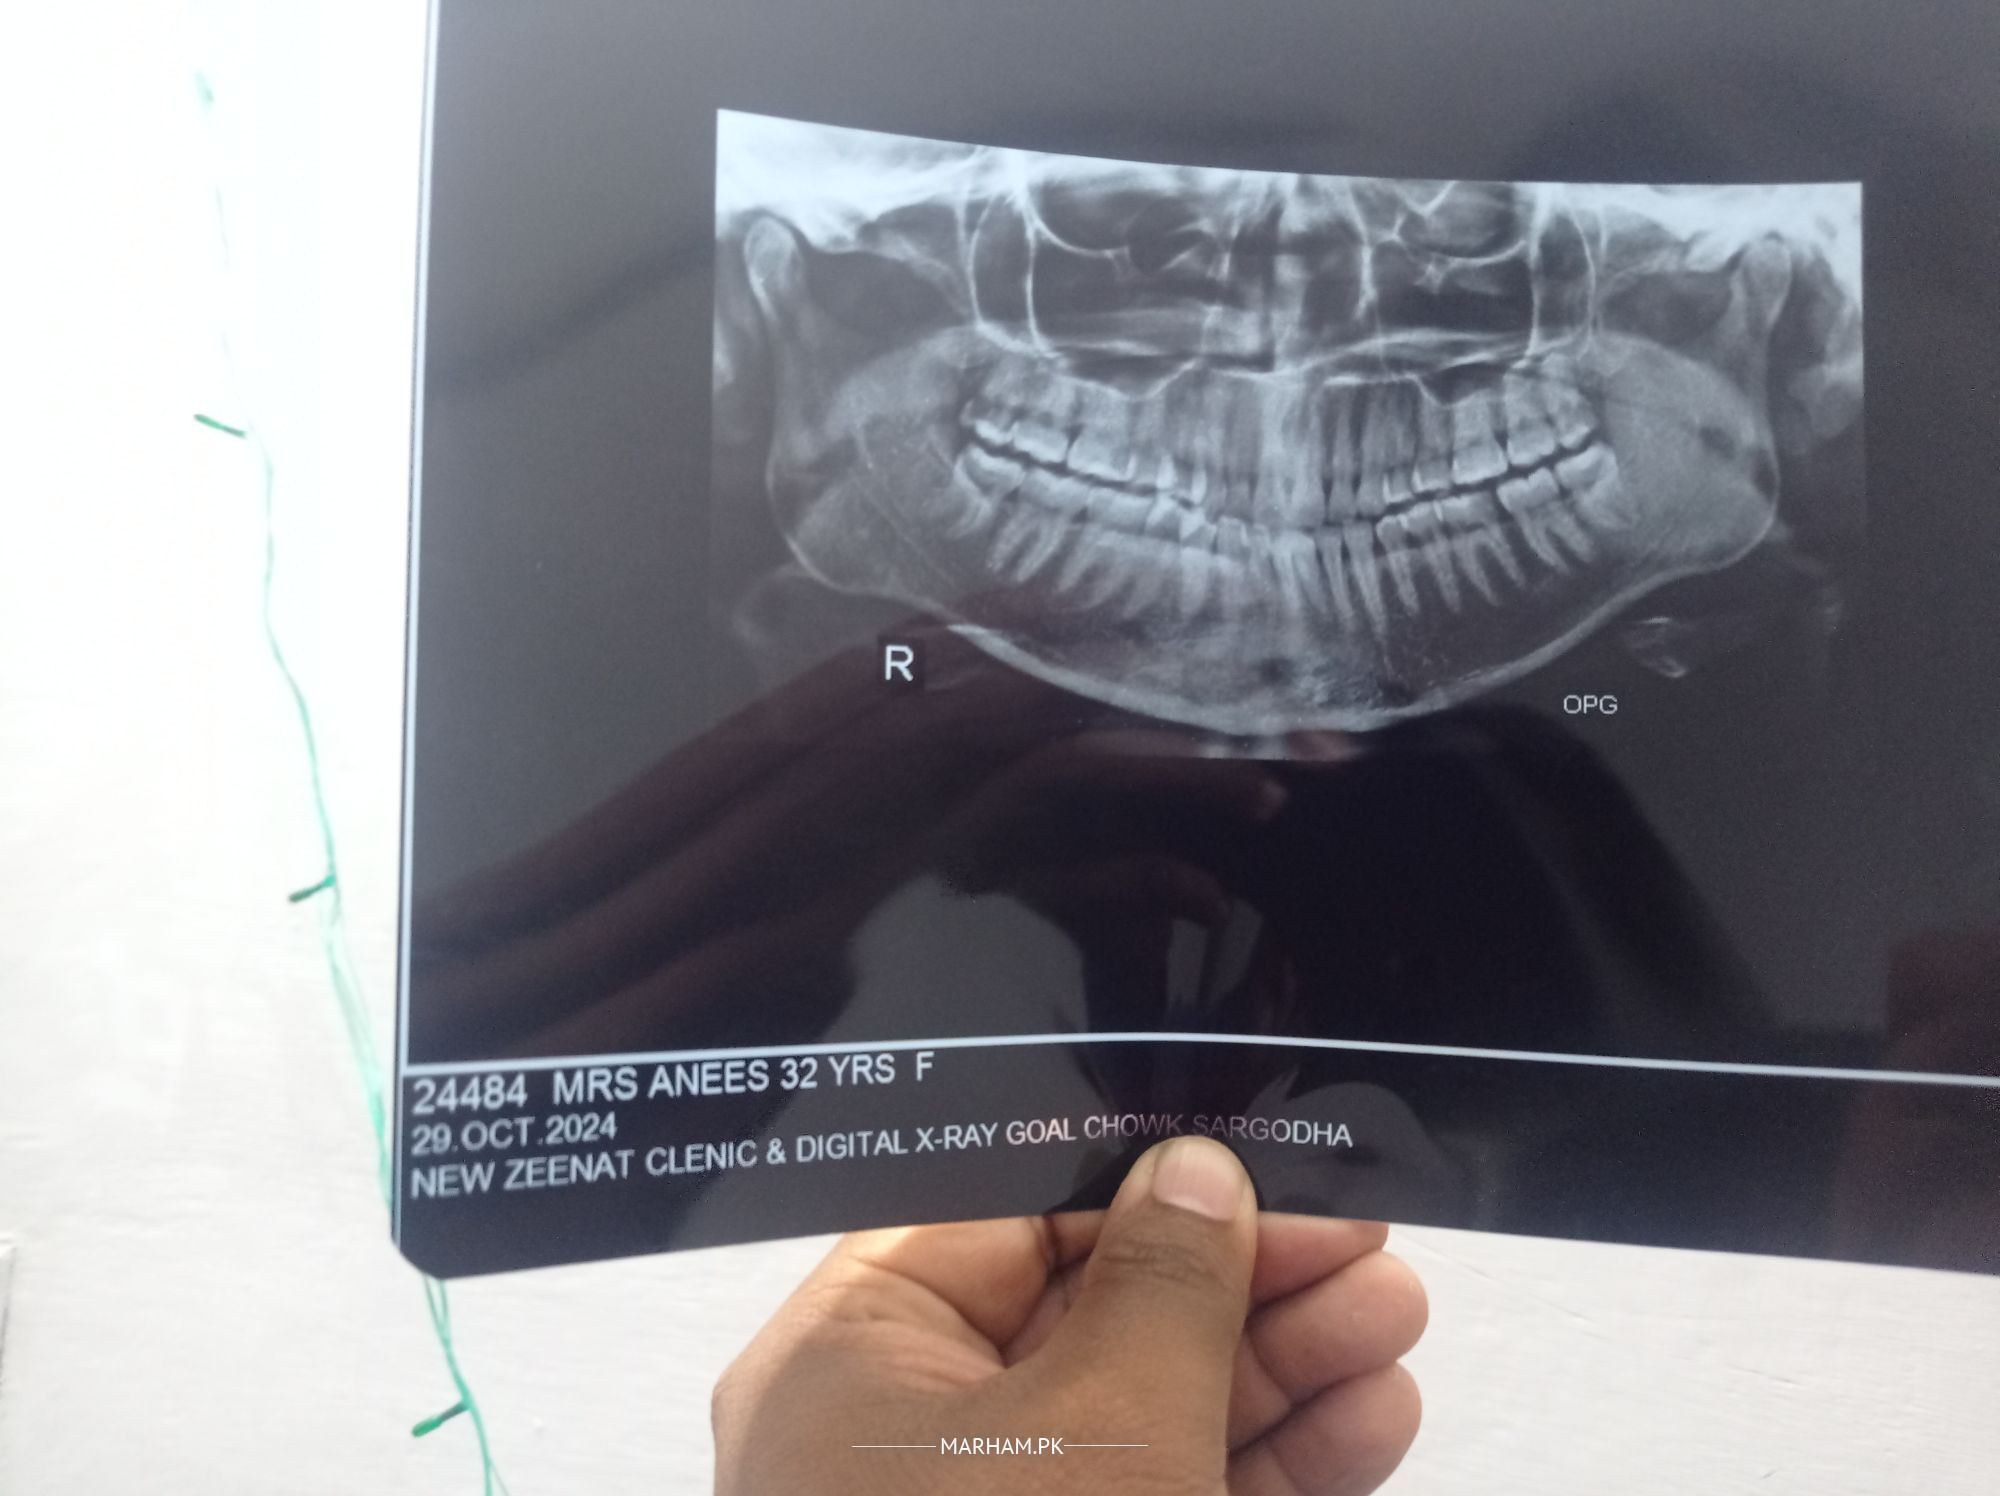

Teeth mein pain bht , swelling nhi ha, neck, head tk pain jaati , ears b bnd ho jaty, medicines sy temporary releif, OPG X ray krwaia, kindly is x ray bry guide kr dein.

ap ka right oper wala dany keera lagny ki vja dy jgrab ho gya.

right upper wisdom tooth seems to be effected

inka right side p upper last tooth ( wisdom tooth ) aqal daar jisy kehty wo carious hy and pain is probably due to that tooth.

extraction karwaly masla khatam hojaiga inshallah

right upper wisdom is carious.referred pain till ear and head

may be due to both upper and lower right side wisdom ( last teeth : aqal darh) get it extracted

Asalam o Alikum. you have caries in your upper wisdom tooth causing intense pain. before any further diagnosis you need proper evaluation clinically on chair side.